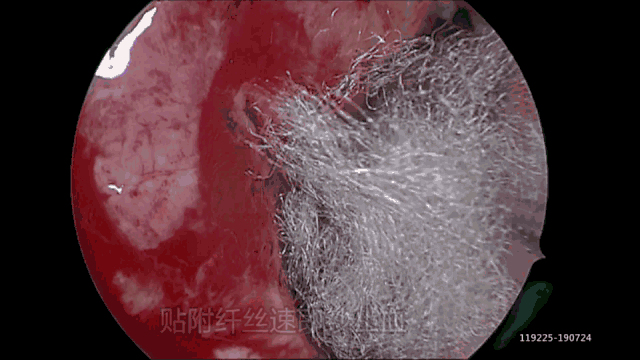

术者在治疗时,结合显微镜下吲哚菁绿造影判定供血动脉、核实畸形血管团块是否切除彻底,为我们术中提供了一个很好的方法和手段,解决了脊髓AVM治疗术中最关切的主要问题。

手术录像显示术者对脑室内解剖结构熟悉,手术思路清晰,术中显微操作和止血技术娴熟,尤其是应用手术导航技术和Endopart通道,最大程度减少对正常脑组织的损伤。术中血肿清除流畅,操作规范:首先清除脑内原发出血部位血肿,对异常血管病灶进行电凝和切除,消除再出血的隐患。然后进入脑室,显示正常脑室内结构和重要血管作为手术标志并加以保护,在精确导航下,逐步清除左侧脑室内和右侧脑室内血肿。手术创面渗血速即纱覆盖止血效果满意。术后常规放置脑室内外引流管,以避免和减少术后脑积水等并发症。患者手术顺利,效果满意,术后CT显示大部分血肿清除,达到手术减压目的,随访未发现脑积水等术后并发症。